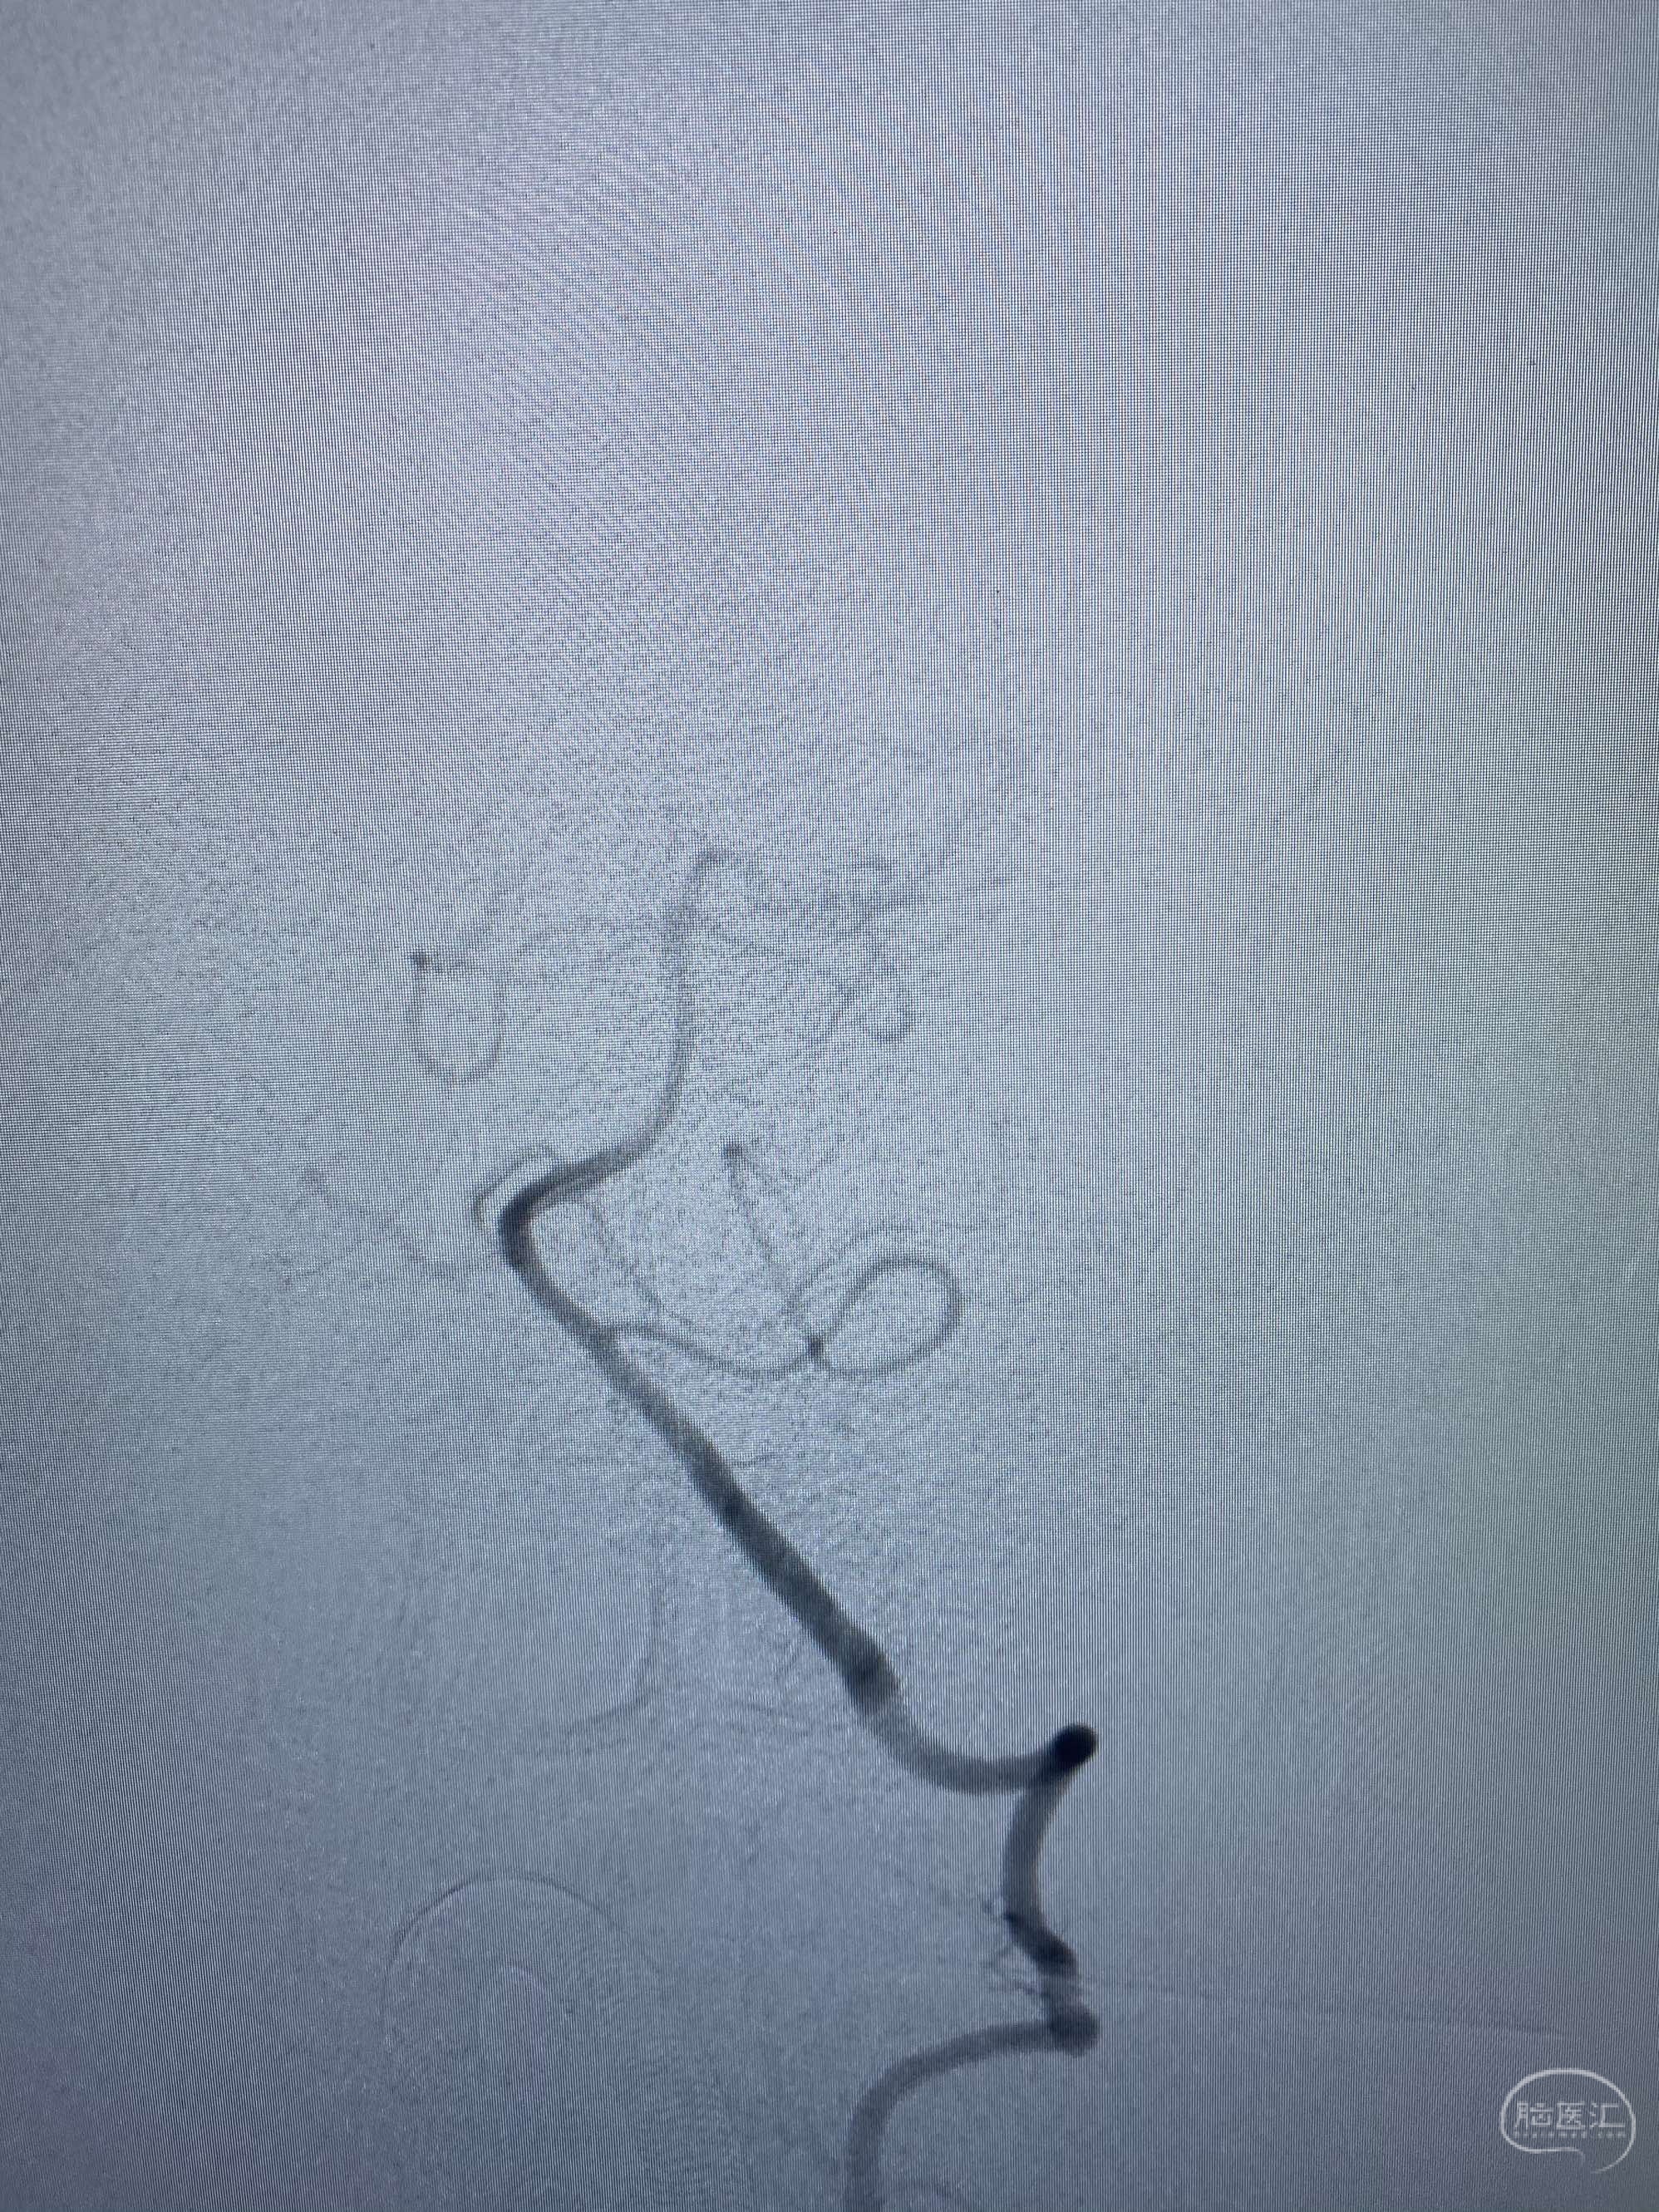

MLS,M79Y,sah,双侧MCA烟雾病,Heubner返动脉瘤,前交通段开窗,细支发出Heubner返动脉,瘤颈细长,瘤颈口比微导管细,弹簧圈2mmx3cm“隔山打牛”填塞治愈,Heubner返动脉保留。